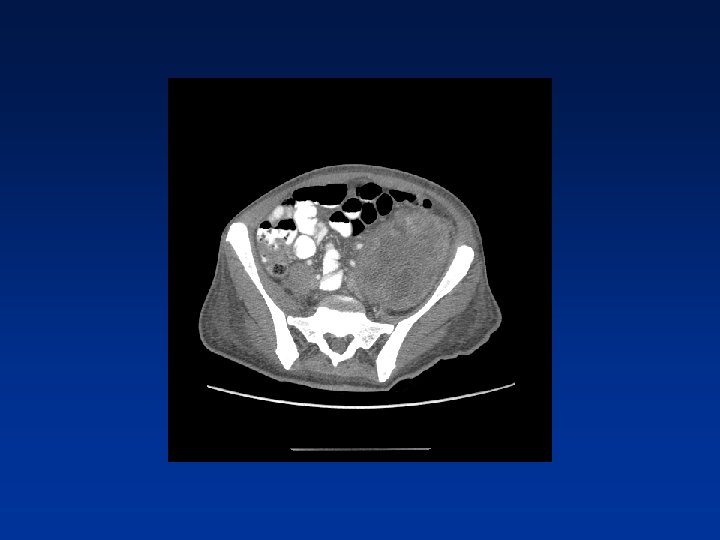

CASE